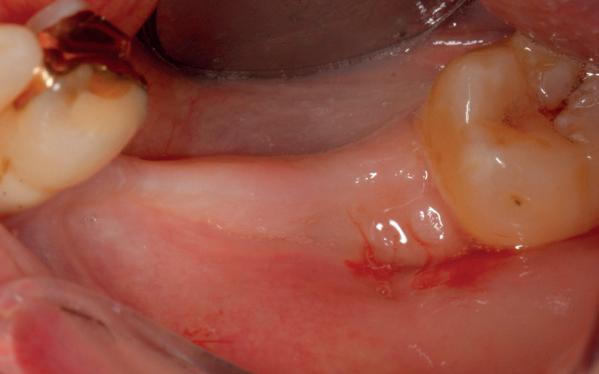

• Aanvulling zachte weefsels met de VISTA techniek en een vrij gingivatransplantaat uit het palatum links en direct dragen van de essix retainer

pincisies met hechtingen naar het buccale en coronale deel getrokken en aldaar ingehecht. Met twee incisies werd ook de emergence profile gecreëerd (afbeelding 6-13). Voor een goede genezing van het

5. Beginsituatie voor behandeling

6. VISTA techniek twee hulp incisies

7. Vervaardiging tunnel met tunnelinstrumenten

8. Geoogst bindweefseltransplantaat uit palatum

9. Na de-epithelialiseren van transplantaat

10. Inhechten van een collageenspons in het donorgebied

11. Middels hechtingen het op de juiste plek trekken van het transplantaat

12. Transplantaat ingehecht

13. Occlusaal beeld verdikking van de zachte weefsels

14. Direct postoperatief plaatsen

van de essix met 2 dummy tanden

15. Twee weken post operatief

16. Creëren van een duidelijke indeuking in de mucosa voor emergence profile